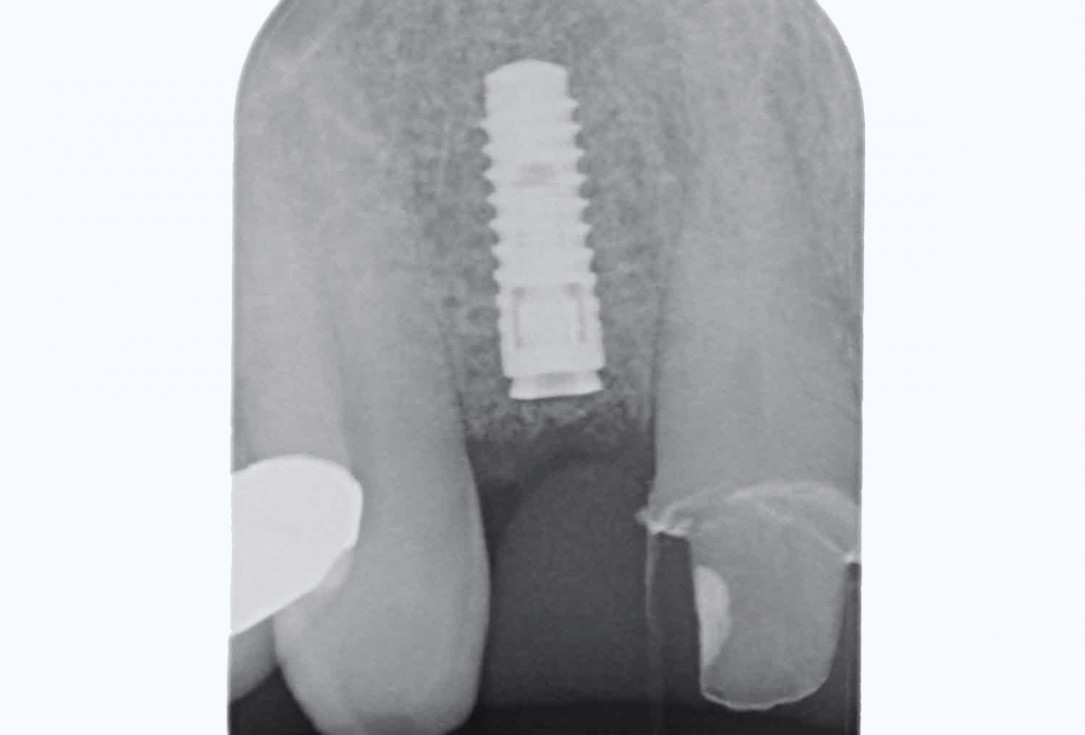

11/19 - Post-op x-ray shows good seating of implantBone augementation with maxresorb® - Dr. R. Cutts